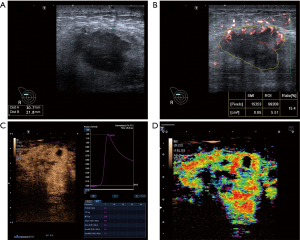

CEUS images contain both qualitative and quantitative parameters, and the scanner equipment’s contrast arrival-time parametric imaging (At-PI) mode was used to assess the qualitative parameters. In At-PI mode, different colors were used to differentiate contrast agent arrival times, ranging from early (red) to late (purple), with a 12-second interval between each color (20). Representative cases in this study are illustrated in Figure 3.

Initially, patients underwent conventional breast US examination in the supine or slightly lateral oblique position. B-mode ultrasound and color Doppler flow imaging (CDFI) images of the lesion were stored. Subsequently, vascularity within the breast lesions was evaluated by SMI, with parameters set to a velocity scale of 1.0–2.5 cm/s, a dynamic range of 21 dB, and a frame frequency of 26–60 frames/s. Lesions were observed in both monochromatic (mSMI) and color (cSMI) modes, and static and dynamic images were stored. The vascular index (VI) was obtained by defining the region of interest (ROI) at the margin of the lesion with the richest signal, and the VI was expressed as a percentage parameter obtained by dividing the vascular encoded pixels in the ROI (11). Three measurements of the VI were performed from different planes. Finally, CEUS was performed following an intravenous bolus injection of 0.015 mL/kg contrast agent Sonazoid (GE Healthcare, Oslo, Norway), followed by a 5–10 mL flush of 0.9% saline solution. The mechanical index was set to 0.08 and the depth was adjusted to 4 to 5 cm. Continuous observation was performed for 120 s, and the images were saved in DICOM format.

On SMI imaging, the microvascular architecture of breast lesion was classified into six patterns, as reported in a previous study (11): type I: no signal; type II: penetrant signals or flow towards the lesion; type III: rim-like signals at the periphery of the lesion; type IV: dot-like/linear/stalked signal in a focal or regional area; type V: wheel-like signals inside the lesion; and type VI: irregular signals with disorganized or branching vessels in different diameters (Figure 2).